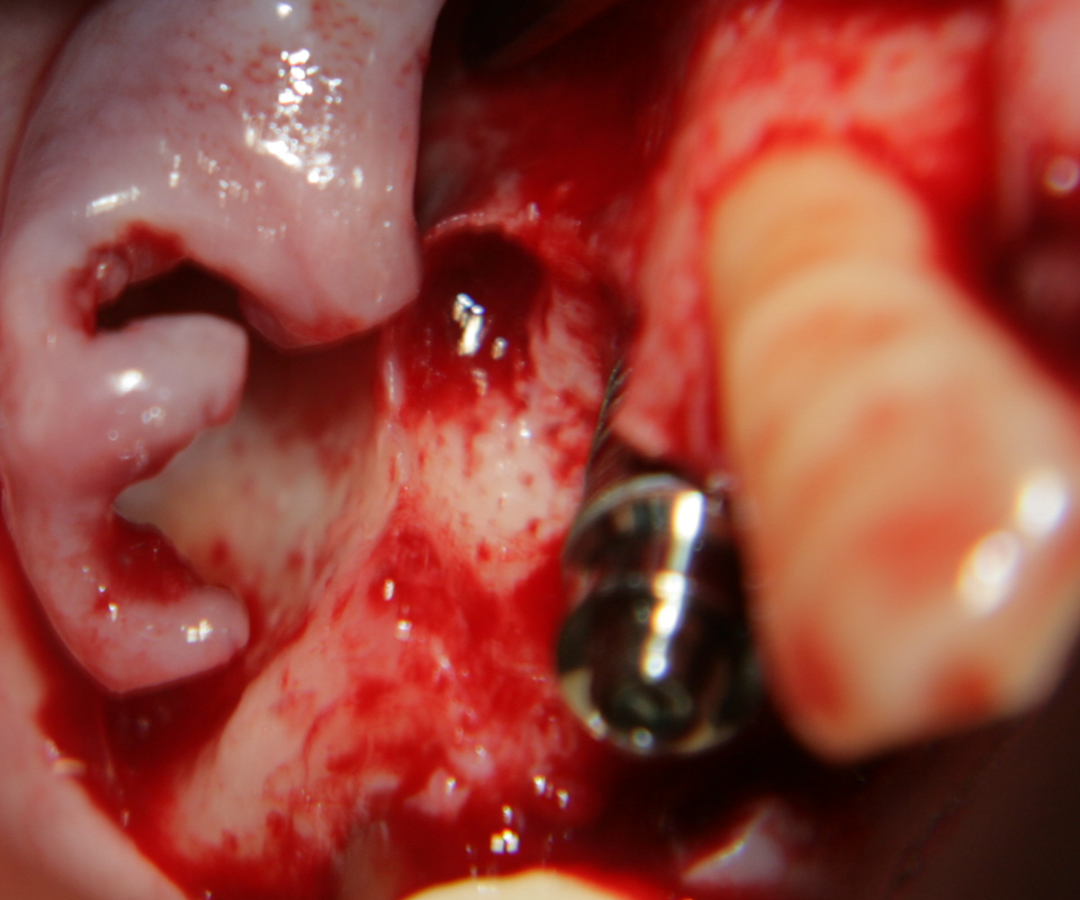

Tent screw - винтове за

фиксиране на титановата мрежа

Титанова мембрана